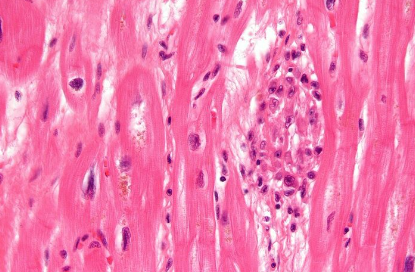

Aschoff's bodies in rheumatic heart disease shows _____ necrosis.